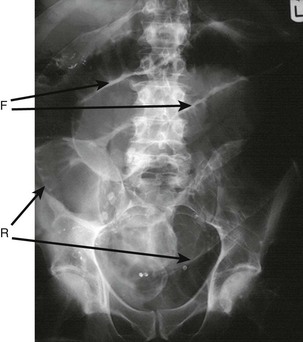

Fig. 32.2 Significance of the relationship of groin lumps to the inguinal ligament

A, B and C are stages in the enlargement of an indirect inguinal hernia. Note that the neck is above the inguinal ligament. A direct inguinal hernia enlarges forwards in position A, but occasionally extends into the scrotum